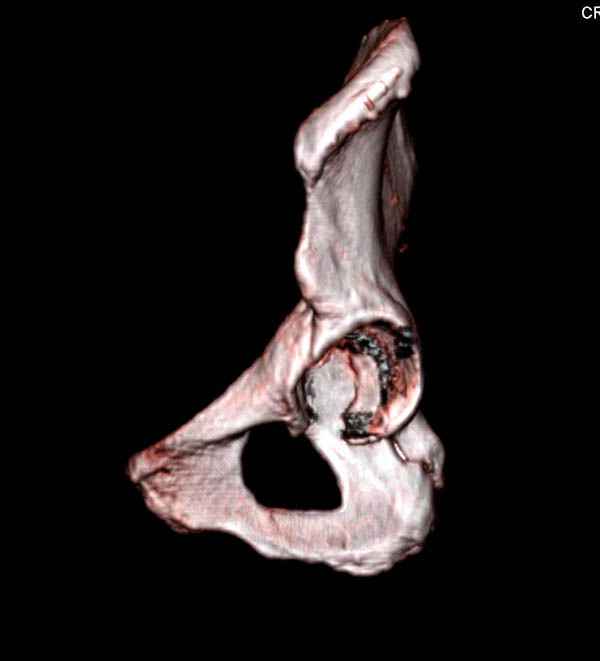

На снимке ацетабулума редко встречающийся очень низкий перелом, наверное, трудно было репозицию через один доступ? Перелом как бы замкнулся в квадрилатеральной поврехности.